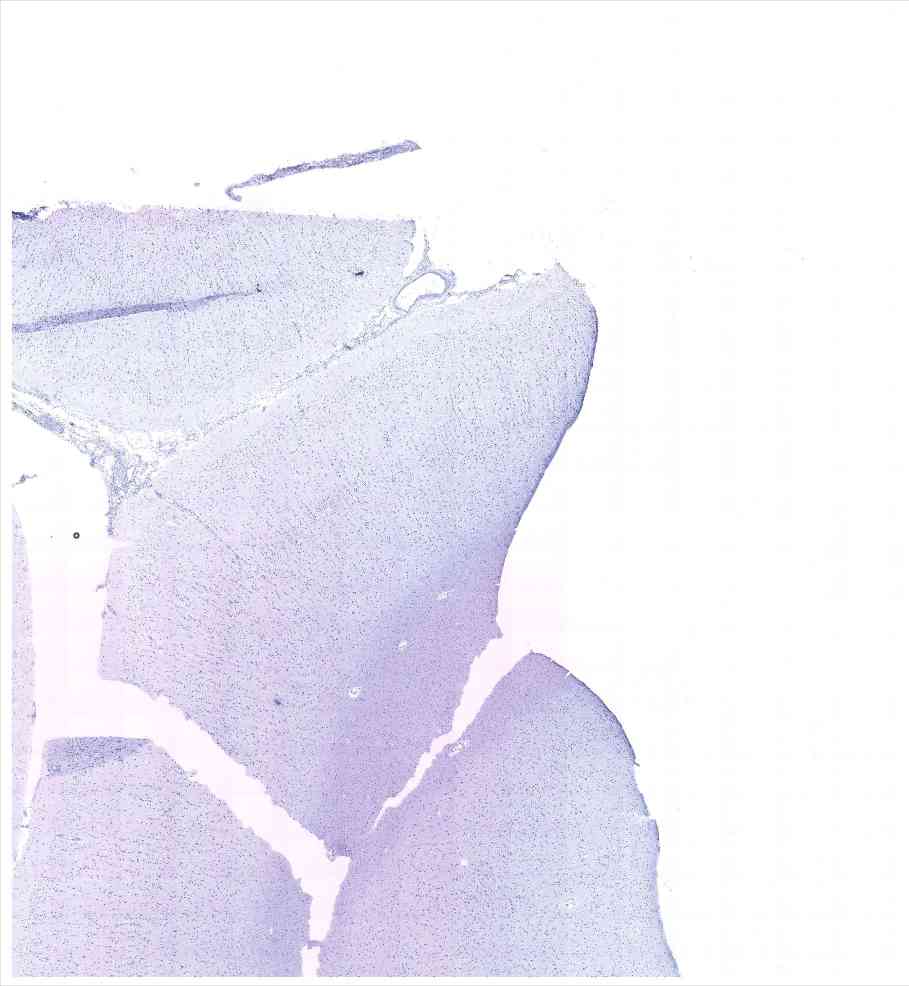

Chip 047 Well C2